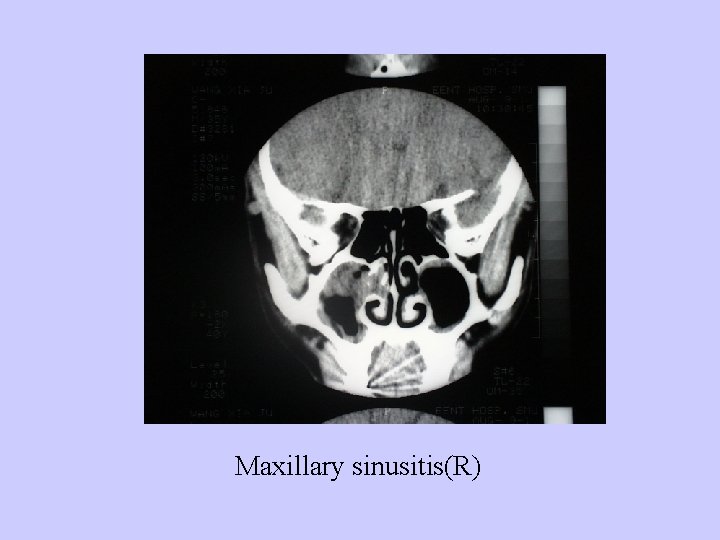

Diagnosis: 1、History; 2、Examination:anterior rhinoscopy, nasal endoscopy 3、Radiological examination:CT or MRI 4、Puncture and irrigation of sinus

Maxillary sinusitis(R)